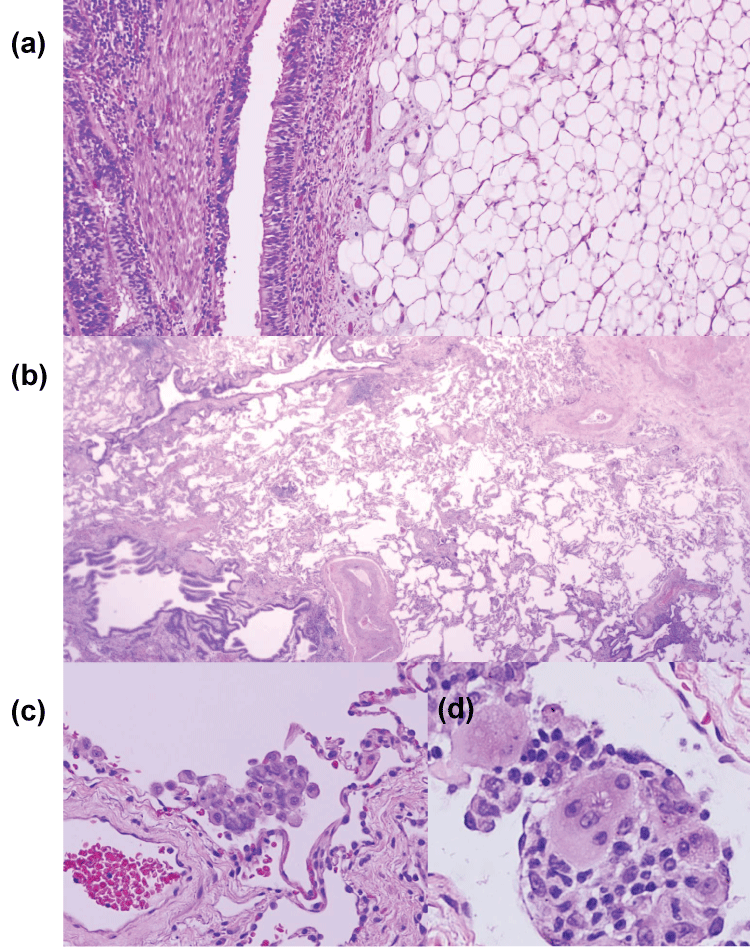

On gross, there was a right upper endobronchial 0.7 x 0.5 x 0.5 cm mass that appeared shiny, well circumscribed, and yellow (Figure 2); it was soft and slippery to the touch. Histology showed endobronchial submucosal mature adipose tissue consistent with endobronchial lipoma along with distal obstruction-related changes, including mild bronchiectasis, peri-bronchiolitis, accumulation of intra-alveolar foam cells, mild emphysematous changes, and rare multinucleated giant cells (Figure 3). AFB and GMS stains, completed to rule-out a mycobacterial reaction, were negative.

Figure 3: (a) Significantly narrowed obstructed bronchus showing mature adipose tissue underneath the respiratory mucosa with distal changes in the lung parenchyma (b) Bronchiectasis, peri-bronchiolar inflammation, and mild emphysematous changes (c) focal accumulation of intra-alveolar foam cells (d) rare multinucleated giant cells with asteroid body